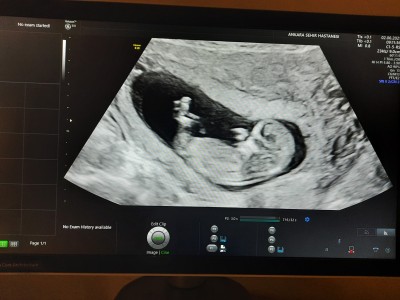

Nub teorisinden anlayanlar bakabilir mi?:)

kizlar ikinci gebeligim ve sıkıntılı geciyor. Lütfen buna mi inaniyosun falan demeyin merak ettim icimde kalmasin istiyorum. Kotu yorum yapacaklar lutfen yazmasin :)

Valla anlamam kuzum ama kıza benziyor bence.

Kıza benzettim

Hayrilisi olsun sanki kiz lgibi

Canım erke gibi ama kiçük bi ihtimal kerisn değil yani

Erkek canım keseye göre. Oval ve yuvarlak kese kız bu şekilde muz gibi duran erkek.